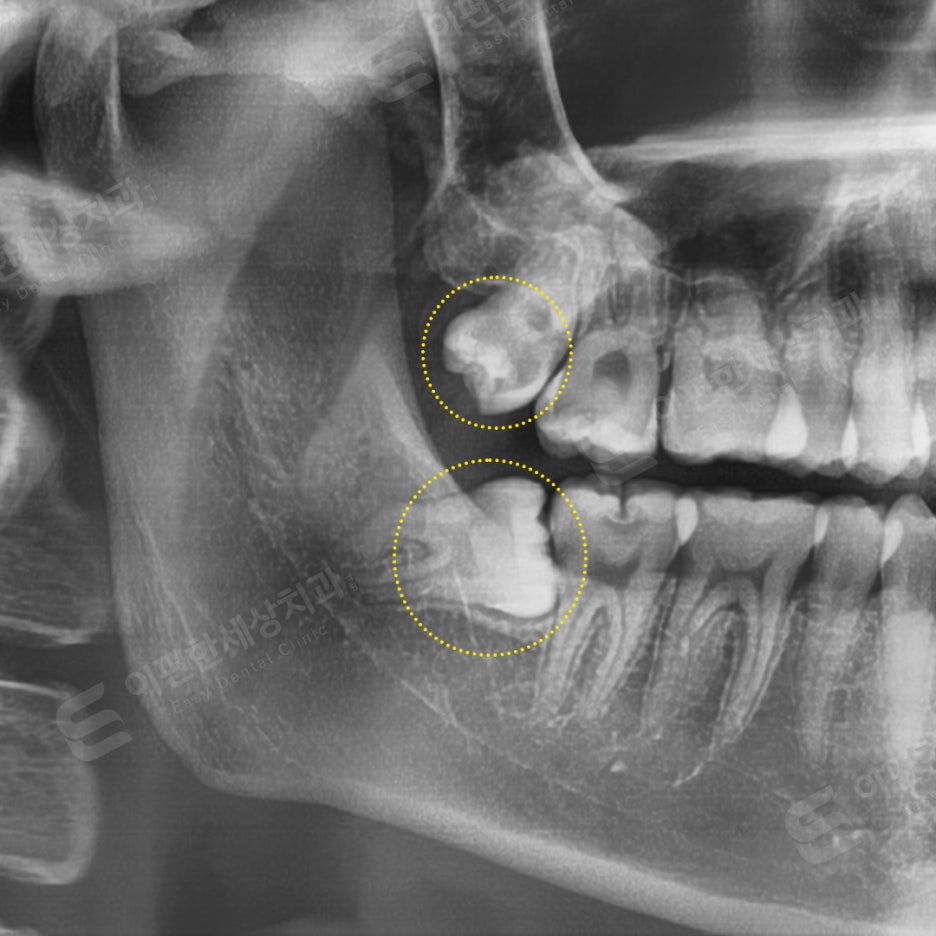

촬영 일자 24.02.16

사랑니 잇몸 통증 호소 발치 케이스

#38 완전매복 발치

#28 일반 발치